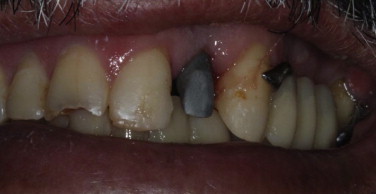

Fig. 3.

Initial clinical aspect with the healing cap in position.

The depth and thickness of the gingival tissue was evaluated to confirm that the abutment metal collar would not be visible. The depth of the gingival sulcus was 2 mm. A chrome–cobalt 20° UCLA was screwed to the implant (Mangran Internacional, Curitiba, Parana, Brazil) to correct its tilting (Figs. 4 and 5).